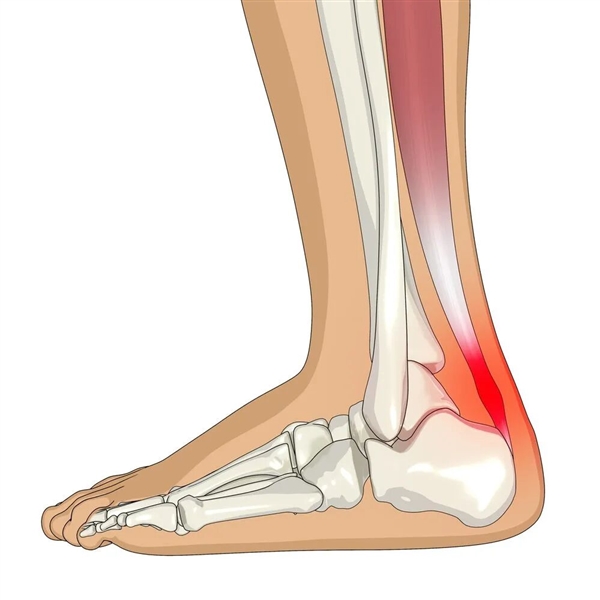

天冷如何保护关节?科学保暖记住这四点,别再只会多穿衣了